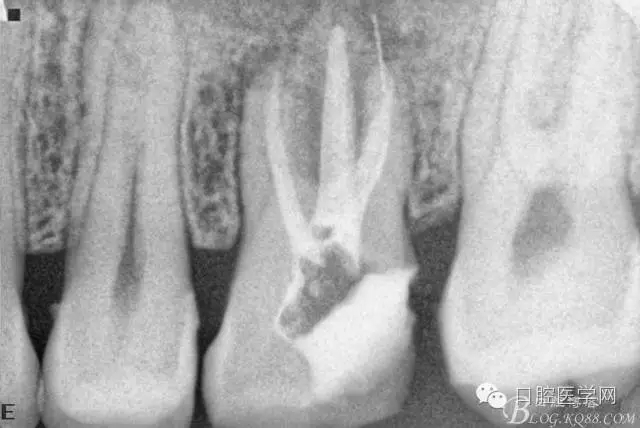

四個(gè)月后患牙Ⅰ°松動(dòng)明顯好轉(zhuǎn),根管內(nèi)無異物,可行根管充填。試主尖片。

根管充填后(遠(yuǎn)頰根內(nèi)有一斷針)。